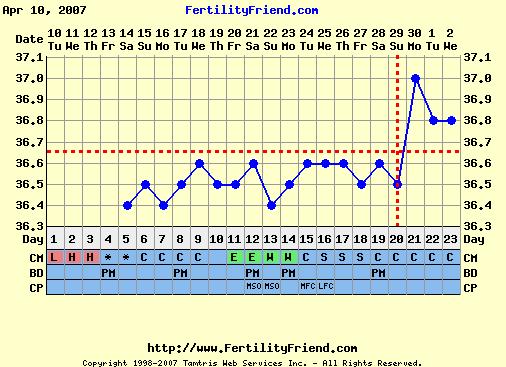

ezt el sem hiszem!!! Megmutatod a görbédet?

Remélem Évának igaza volt és lesz azért pé-d, csak esetleg csúszik az egész!!